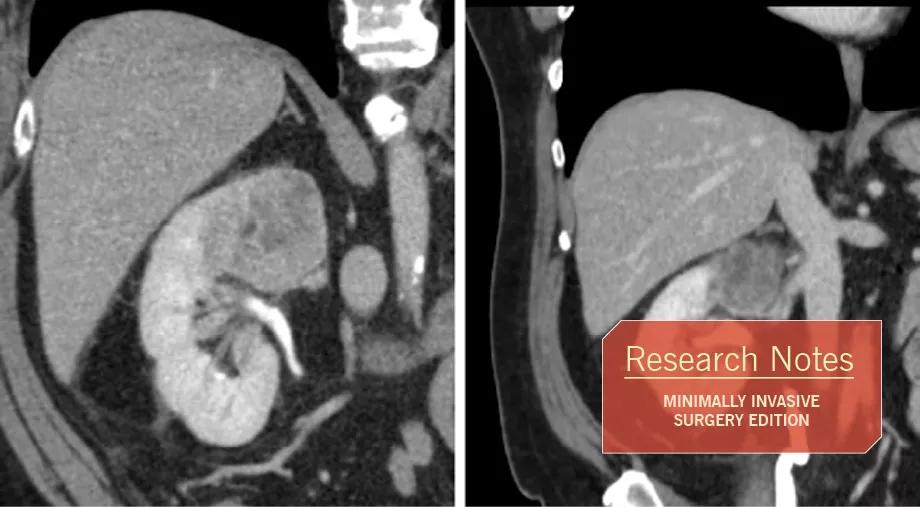

In other patients with preexisting chronic kidney disease (CKD) and challenging tumor size and location, PN may be feasible but the amount of parenchymal mass and function that would be lost with the surgery would be unacceptable, placing the patient at increased risk for adverse outcomes (See Figure). A recent analysis showed that new baseline glomerular filtration rate (GFR) after renal cancer surgery is a strong predictor of renal stability and long-term survival, particularly for patients with preexisting CKD.

Overall, the mean parenchymal volume that could be saved with PN increased from about 100 cc to 175 cc, and functional preservation paralleled this, representing another significant gain with this approach. As the tumor pulled away from the hilum, substantially more parenchyma, and thus function, could be saved during tumor excision and reconstruction (See Figure). Urine leaks were diagnosed in five patients after PN and seven received perioperative blood transfusion, although only one required angioembolization.

Figure. A 61-year-old with a solitary right kidney presented with a 5.4 cm mass within the upper pole and extending near the hilum. The RENAL score was 10 and the tumor did not appear to be well encapsulated. The GFR was 38 ml/min/1.73m2. While PN was possible, it would not save optimal amounts of parenchyma and function. After eight weeks of pazopanib, the tumor was downsized to 3.8 cm with a RENAL score of 8, and the tumor pulled away from the hilum. The tumor also appeared well- encapsulated and demonstrated extensive necrosis. PN was performed with cold ischemia time of 38 minutes. Recovery was uneventful. Eighty-two percent of the parenchyma was preserved and the final GFR was 34 ml/min/1.73m2.